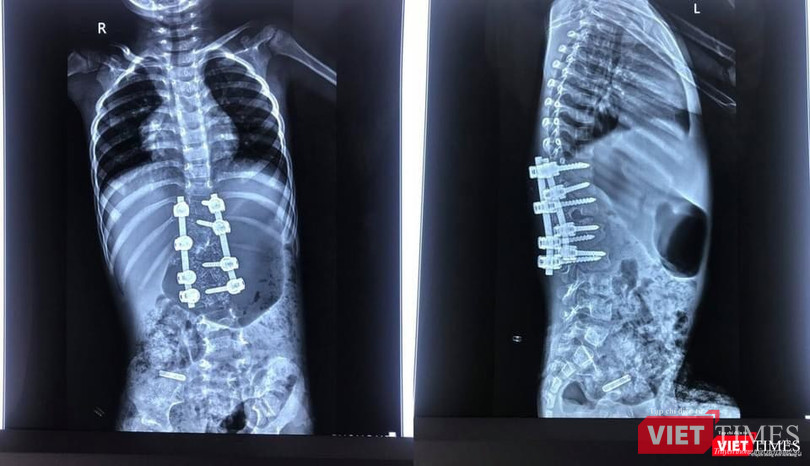

| Hình ảnh X quang ca cong vẹo cột sống của bệnh nhi 3 tuổi (BVCC) |

Bác sĩ cho biết sau phẫu thuật biến dạng được nắn chỉnh rất tốt |

Sau mổ, bệnh nhi đã được nắn chỉnh tốt biến dạng cong vẹo cột sống, không có tổn thương thần kinh. Bệnh nhi hồi phục thuận lợi, hai chân vận động bình thường. Bé đang tập ngồi và đi lại được, tiểu tự chủ.

Hình ảnh X-quang sau mổ cho thấy biến dạng được nắn chỉnh rất tốt, còn giữ được chức năng 3 đĩa đệm cuối cùng của cột sống thắt lưng. Ca phẫu thuật thành công mang lại một dấu mốc với khoa Chấn thương - Chỉnh hình Cột sống (B1-D) và khoa Gây mê hồi sức (B5) của BV 108, mở ra cơ hội cho nhiều bệnh nhi khác.